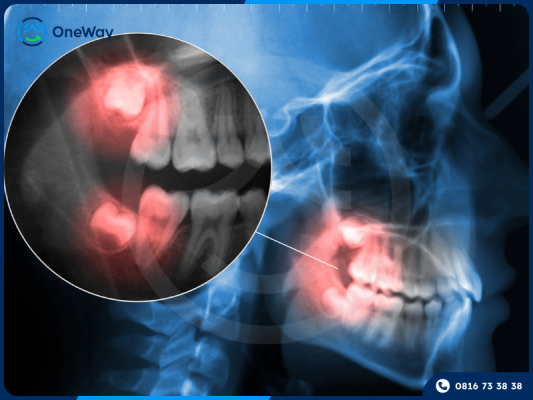

Thông thường, răng khôn khi mọc lên có thể gây ra nhiều phiền toái. Do các răng vĩnh viễn đã chiếm chỗ trên cung hàm, răng khôn thường gặp khó khăn khi trồi lên, dễ mọc lệch hoặc mọc ngầm dưới nướu, dẫn đến nhiều biến chứng nguy hiểm. Ngoài ra, việc vệ sinh khu vực này cũng trở nên khó khăn, tạo điều kiện cho vi khuẩn tích tụ và hình thành mảng bám, lâu dần gây viêm lợi trùm răng khôn.

Lợi trùm răng khôn là tình trạng mô nướu bao phủ một phần hoặc toàn bộ răng khôn, cản trở quá trình mọc răng. Điều này không chỉ gây đau nhức, sưng viêm mà còn có thể ảnh hưởng đến răng bên cạnh, làm tăng nguy cơ viêm nhiễm và biến chứng nghiêm trọng.

- Trong trường hợp răng khôn mọc ngang hoặc mọc nghiêng, việc cắt lợi trùm không mang lại hiệu quả triệt để, vì không thể giải quyết tận gốc các biến chứng do răng khôn mọc lệch gây ra. Khi đó, bác sĩ thường chỉ định nhổ răng khôn để bảo vệ sức khỏe răng miệng và ngăn ngừa những biến chứng nghiêm trọng có thể xảy ra.